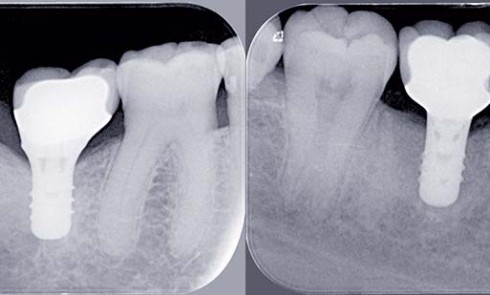

Article réservé à nos abonnés Edentement unitaire postérieur et abstention thérapeutique : mythes et réalités

Malgré l’amélioration de la santé orale observée dans les pays industrialisés ces dernières années, l’extraction dentaire reste un acte fréquent....

Article réservé à nos abonnés Prothèse implantoportée unitaire et édentement unitaire postérieur : facteurs de succès prothétiques

La mise en place de restaurations prothétiques unitaires sur des implants situés dans les secteurs postérieurs (zone des prémolaires et...